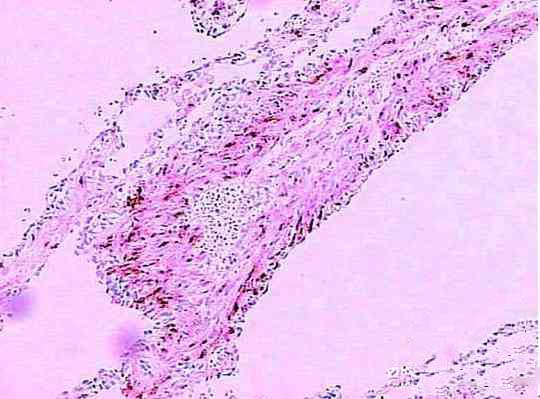

病理改变:肺间质、支气管、血管和淋巴管内出现未成熟的平滑肌弥漫性异常增生。平滑肌细胞增生主要累及肺,也可累及肺外组织。